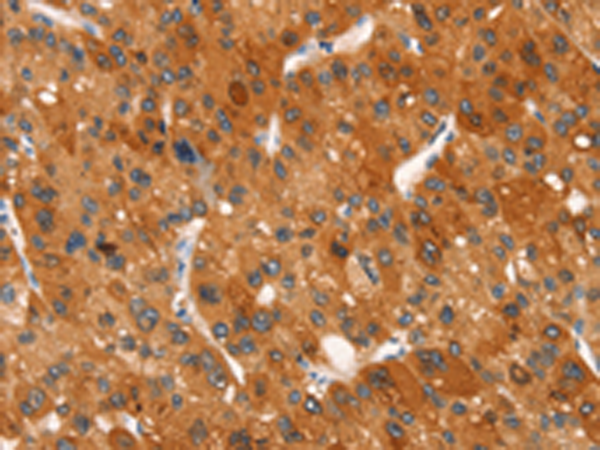

IHC positive control: |

Human liver cancer |